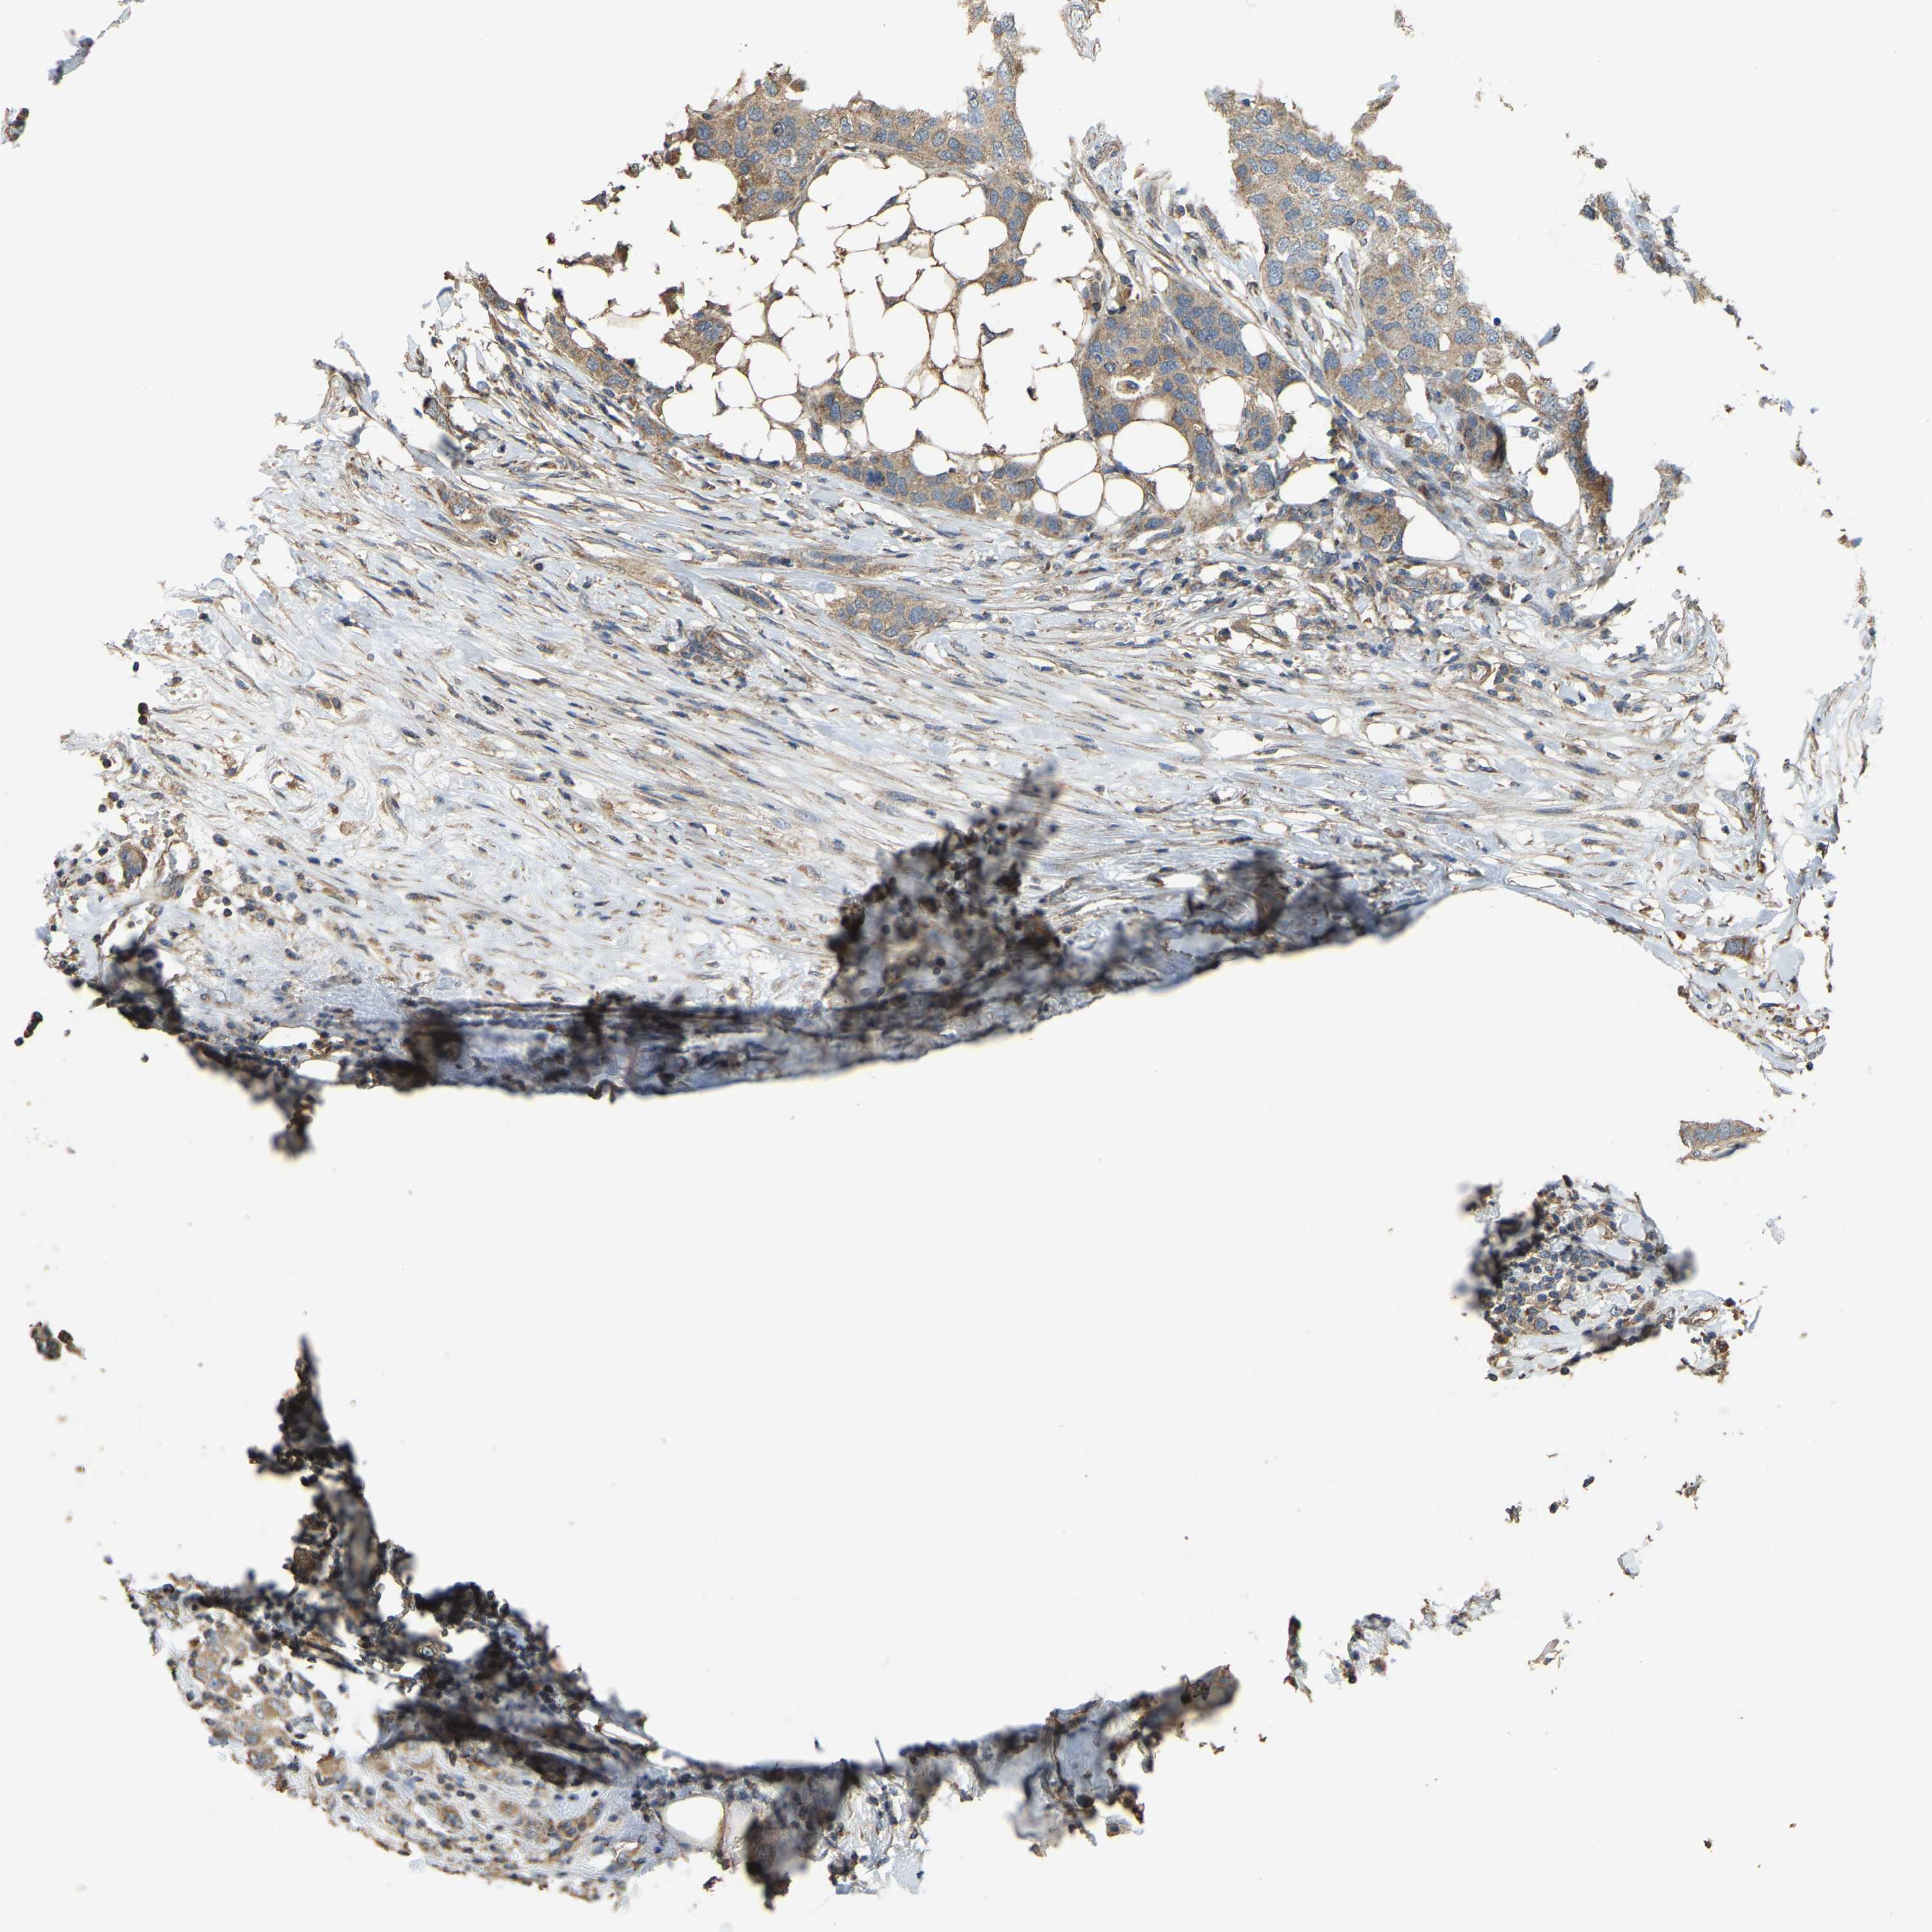

Breast cancer

Human cancer